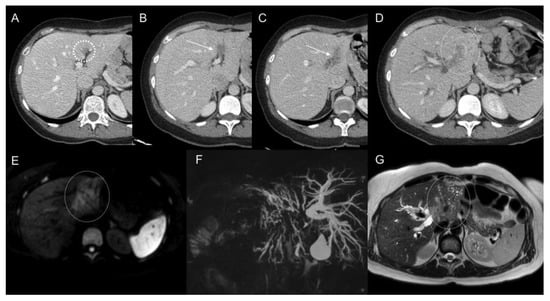

- Low, R.N.; Barone, R.M. Combined diffusion-weighted and Gadolinium-Enhanced MRI can accurately predict the peritoneal cancer index preoperatively in patients being considered for cytoreductive surgical procedures. Ann. Surg. Oncol. 2012, 19, 1394–1401. [Google Scholar] [CrossRef] [PubMed]